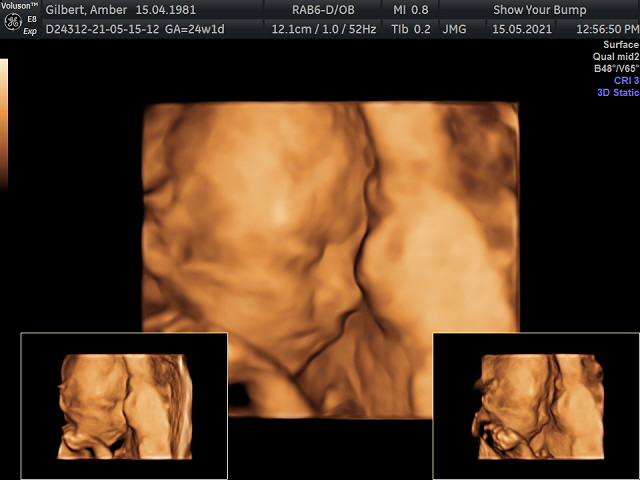

Throughout the rest of our pregnancy we had extra scans planned to check on babies growth, it seemed like almost every 2 weeks we had a scan either at our local hospital or at the fetal medicine unit in Manchester. Fortunately at every growth scan, there were never any concerns about growth or any other issues. We did have a private 4D scan which had been a gift from my sister for my 40th. It was really nice to have a scan for pleasure and not for medical purposes, just to see our little baby as a little baby.